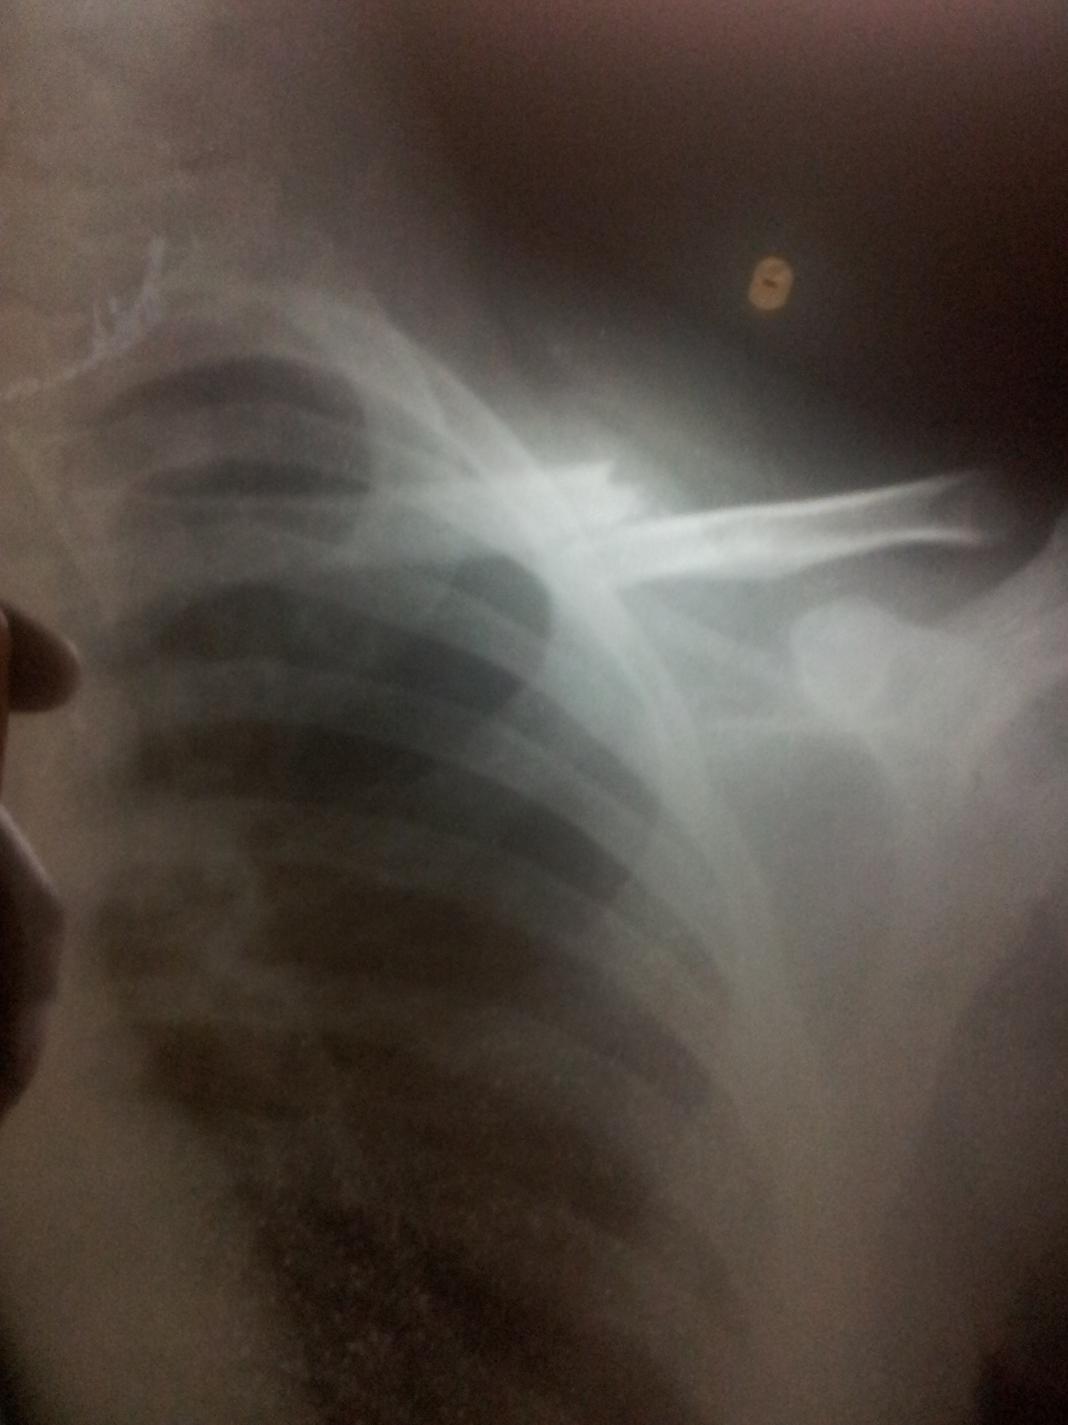

Very bad day for me :/ 1.jpg

Very bad day for me :/ WOOW!

That yellow thing is a bullet? 😲

WOOW!

That yellow thing is a bullet? 😲 Gosh don't even say that 😝 thats a defect in the x-ray its the collar bone that broke because i was stupid enough to do a forward flip.....3 weeks on a sling.

Typing is very slow and so many missclicks.

Gosh don't even say that 😝 thats a defect in the x-ray its the collar bone that broke because i was stupid enough to do a forward flip.....3 weeks on a sling.

Typing is very slow and so many missclicks. Oh, my bad. But, seriously, that yellow thing really looks like a bullet 😝

Collar bone huh? ouch. No worries, you ll be back in action soon. 😁